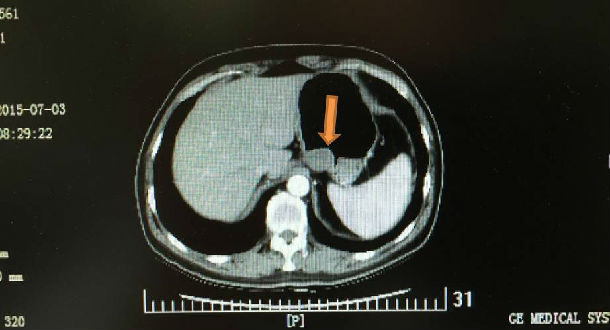

2、影像学检查:增强腹盆CT或核磁共振成像。

CT表现:GIST在影像学检查表现为向腔外或腔内生长或沿胃肠壁浸润,大小不等,形态多为类圆形肿块,少数也可为不规则形,大部分边界完整。肿瘤体积较大的肿块内常常因为缺血坏死、或出血导致囊性变而显示低密度灶。肿块边缘可出现钙化,增强后实性部分多为中度以上强化,病变多数血供丰富,中高度强化,伴瘤周多迂曲供血血管。

胃贲门附近的间质瘤,腔内生长,大小约3cm